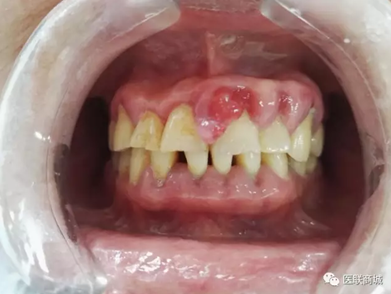

口腔衛(wèi)生狀況較差,牙石(++),軟垢(++),全口牙齦紅腫增生明顯,11、21、22、23牙齦增生明顯,11、21齦乳頭呈菜花樣增生,質(zhì)軟,界清,觸痛(-),易出血,全口PD=5-7mm,下前牙舌側(cè)GR=1-2mm,咬合關(guān)系基本正常,未見明顯咬合創(chuàng)傷。

曲斷示:全口牙齒牙槽骨水平吸收根長1/2-2/3。